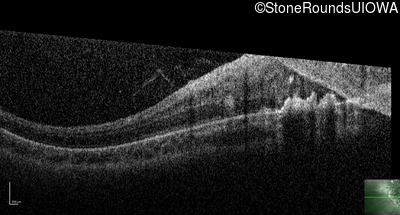

This 9 year old male was noted to have some crossing of his eyes at 2 months of age and the eye exam which followed identified a retinal lesion in the right eye. When he was six years old an epiretinal membrane was noted in his left eye. Two years later it was decided that it was a thin hamartoma in that eye as well. He underwent neuroimaging at age 7 which identified bilateral acoustic neuromas.

| Age at visit: 10 years |

| Age at visit: 11 years |